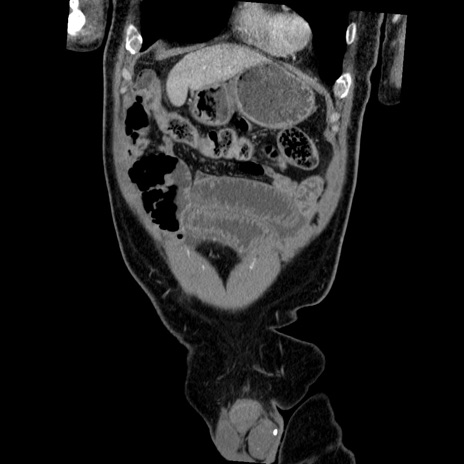

症例22(冠状断像)

【症例】50歳代男性

【主訴】腹痛

【現病歴】AVMからの被殻出血のため回復期リハ病棟入院中。 本日午後3時頃急に下腹部痛が出現した。

【既往歴】AVM、被殻出血、虫垂炎、高血圧

【身体所見】意識晴明、左半身不全麻痺、会話の理解は良好、36.5°C、腹部:膨隆、全体に板状硬、下腹部正中に圧痛点あり、反跳痛-、筋性防御不明、右下腹部にope scar

【データ】WBC 9400、CRP 0.06